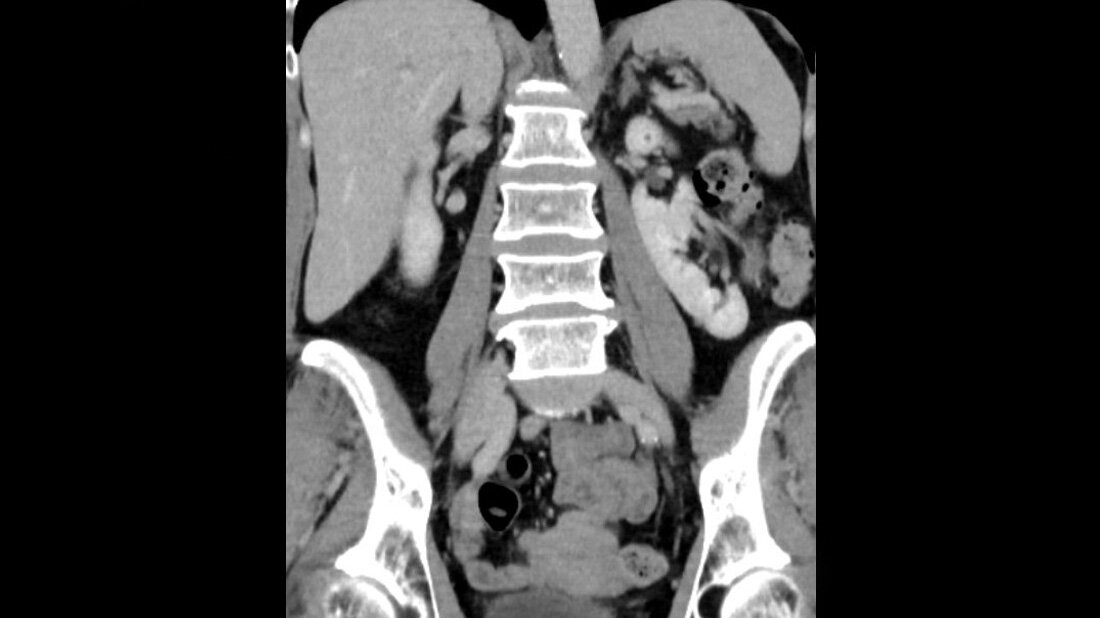

Anomalien und Normvarianten – Interne Veränderungen 2.14: Nierenmalrotation

Der obere Harntrakt ist die von den meisten kongenitalen Anomalien betroffene Region des Menschen. Eine Malrotation kann mit anderen Anomalien wie Nierenektopie oder Harnleiterduplikatur vergesellschaftet sein. Die intravenöse Urografie ist durch die CT- und MR-Urografie ersetzt worden. Die Kombination von Nierenmalrotation und Hydronephrose kann eine chirurgische Herausforderung sein.

Schlüsselwörter: Nierenmalrotation, CT, MRT